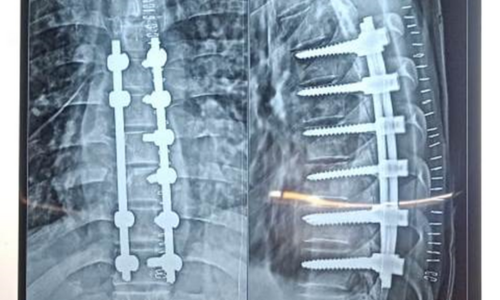

Posted on Nilesh KaduTrustindex verifies that the original source of the review is Google. I visited Dr. Nitish Agarwal for my severe back pain and shoulder issue. He checked my MRI very carefully and gave the perfect diagnosis. Yesterday, he performed the procedure (Root Block and Shoulder Injection), and it was completely painless. He is an expert and targeted the exact nerve point causing the trouble. Very helpful and humble doctor. Highly recommended for anyone with spine problems.Posted on Raju GorkhaTrustindex verifies that the original source of the review is Google. I was unable to make movement and suffered from right foot drop which is equal to halfway paralysis. Dr. Nitish Agarwal performed very fine microscopic surgery on L3, L4 & L5. After 90 days under his treatment I could go for a walk min. 6 kms a day, I have started my regular activities after 120 days. Thank you so much Dr. Nitish Agarwal sir.Posted on Pururaj GuravTrustindex verifies that the original source of the review is Google. I was suffering from severe back pain, and Dr. Nitish Agrawal has been extremely supportive throughout my treatment. He listened carefully, explained everything clearly, and guided me very well. His treatment has really helped me recover. He is one of the best spine specialists — highly recommended!Posted on Vinal AgrawalTrustindex verifies that the original source of the review is Google. I had consulted many doctors before Dr Nitish for my mother's spine issue,most recommended complex procedures and surgeries. Fortunately we found Dr Nitish and it has been life changing for my mother,she was in immense pain before the simple surgery he did. It's rare to find a surgeon who explains everything in detail and provides such exceptional care even after the surgery. I Would highly recommend him.Posted on Ajinkya MohadkarTrustindex verifies that the original source of the review is Google. My mother had sustained a fracture to her right hand wrist and we were worried about her recovery due to age factor. One of our family Doctor referred us to Dr. Nitish Agrawal and we visited Dr. Nitish Sir. Dr. Nitish sir ensured that my mother don't need a surgery and treated her by application of plaster (temporary and then cast-iron or Firm plaster) with certain orthopaedic treatment to hand and prescribed oral medication for ensuring recovery is faster without any surgery. Attaching the photo of xray which shows recovery of wrist bone which has rejoined and we are still continuing treatment to ensure my mother is fully recovered and is fit. Thank you Dr.Nitish Agrawal for your support.Posted on Samadhan LokhandeTrustindex verifies that the original source of the review is Google. Hi everyone, myself Samadhan. I was suffering from severe spine pain for a long time, and one of my friends suggested I visit Dr. Nitish Agarwal. Honestly, that was the best advice! Dr. Nitish listened to my problem very patiently, explained the cause in detail, and gave me the right treatment. I started feeling better within a short time. He is very polite, knowledgeable, and truly cares for his patients. I highly recommend Dr. Nitish Agarwal for anyone dealing with spine or back pain. Thank you, doctor, for your excellent treatment and support!Posted on POOJA JAGDALETrustindex verifies that the original source of the review is Google. Dr. Nitish Agrawal is an excellent spine specialist who patiently listens, explains the problem clearly, and provides the best treatment options.Posted on vipul pardeshiTrustindex verifies that the original source of the review is Google. Dr.Nitish sir is an incredible surgeon. I had excellent results from my recent spine surgery. The entire process, from consultation to recovery, was handled with professionalism and care. The outcome has been life-changing. I highly recommend Dr.Nitish agarwal to anyone in need of a spine surgeon.Posted on Deepak JadhavTrustindex verifies that the original source of the review is Google. A few months back I took treatment for my back pain from dr. Agarwal sir ...last 7-8 years i was suffering with low back pain,unbale to stand for more than 10 minutes..My low back hurts continuously, and also left leg pain was unbearable....i try every possible way of treatment from various suggestion...After several treatment...one of my relative suggested dr. Nitish Agarwal sirs name then I visited Dr. Nitish Agarwal sir in clinic. He suggested me x ray and MRI. On that basis he advise me caudal Block with root block with facet block for pain management. After block my pain goes with in a week. He advise me regular Physiotherapy at home. Now after regular exercise I am pain Free. Dr. Nitish Agarwal is a good doctor for any spine related problem.... Thank u dr. Agarwal Sir 🙏Posted on Kumar BTrustindex verifies that the original source of the review is Google. My wife had major infection in neck and lower back. She was bedridden. her legs and hands were weak. Then we admit her under Dr. Nitish Agarwal sir and did MRI. He explained that she is having major infection in cervical and lumbar spine. Due to infection her spinal cord is compressed so she was not able to walk. Then sir did operation for neck and removed infected tissue and spinal cord is freed and put a plate. Her lower back is treated with medicine only. She was given 2 months antibiotics by saline and 5 months oral antibiotics were given. He also advised regular exercise. After 15 days of surgery she started walking with support. Now after 1 year she is completely alright and walking like a normal person. She is regularly doing all her activities. Now she can also travel by 2 wheeler. Thank you to Dr. Nitish Agarwal sir for his expert work in spine. I recommend Dr. Nitish Agarwal for any spine related problem.